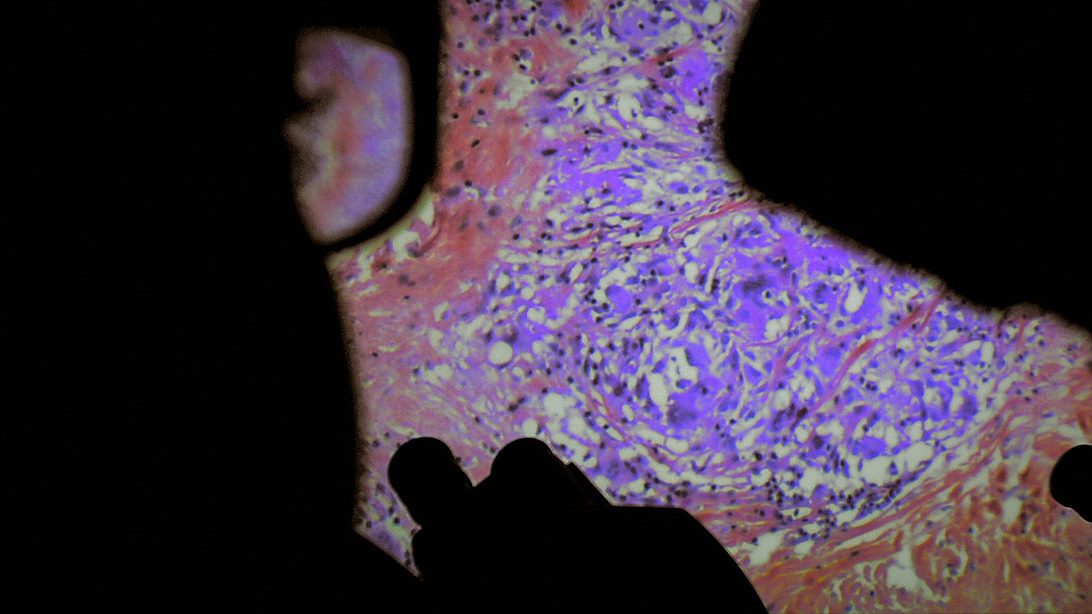

De Humani Corporis Fabrica